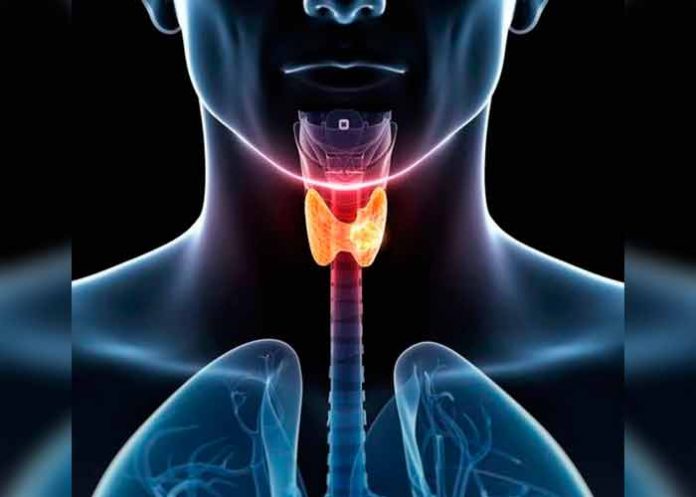

Madrid, 24 abr (EFE).- La incidencia del cáncer de tiroides va en aumento y, aunque estos tumores responden bien al yodo radiactivo, para algunos pacientes el tratamiento no sirve. Ahora, un equipo de investigadores ha descrito una molécula responsable de este cáncer y cuya inhibición reduce el crecimiento tumoral.

El cáncer de tiroides, que se origina en la glándula tiroidea, se trata con yodo radiactivo pero para algunos pacientes no funciona, por eso se buscan nuevas dianas moleculares y terapias.